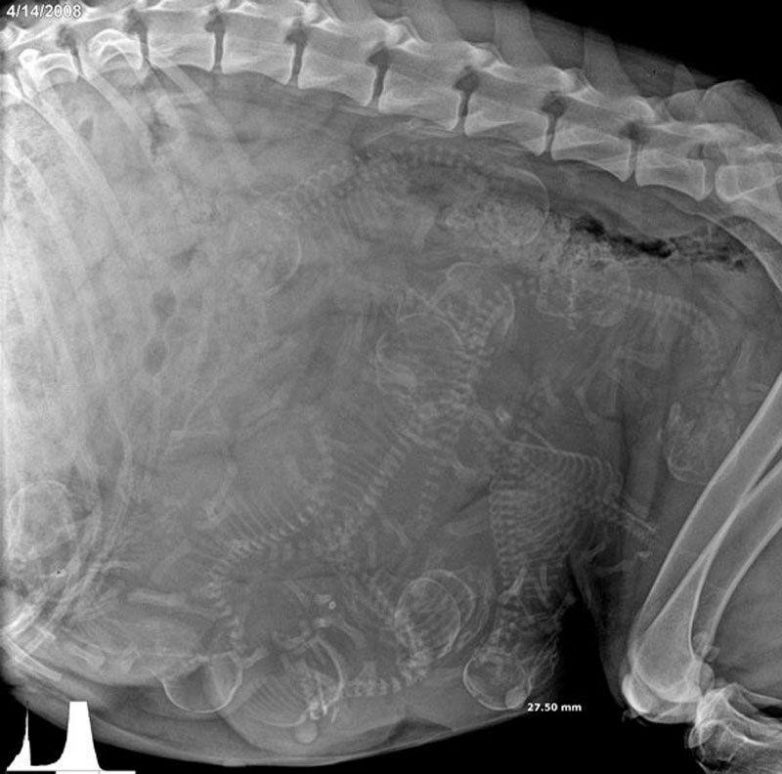

И все у вас будет внутри нормально (рентген беременной собаки)